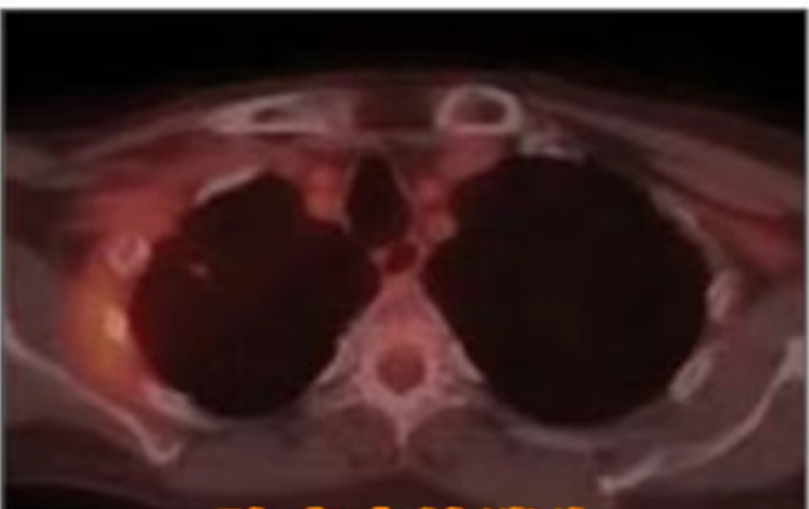

A follow-up PET-CT scan revealed that the irregular nodule near the right upper hilum had become blurred, surrounded by dense, fibrotic streaks clearly visible on imaging, with extremely low metabolic activity. These findings indicated that the tumor was completely necrotic — and the lymph node metastases had also disappeared entirely.

Results and Follow-up

At 11 months post-treatment, PET-CT imaging showed no evidence of active disease, with only residual scarring visible. PET results were negative for metabolic activity. The patient remained in good overall condition, with no reported adverse complications following CyberKnife treatment.